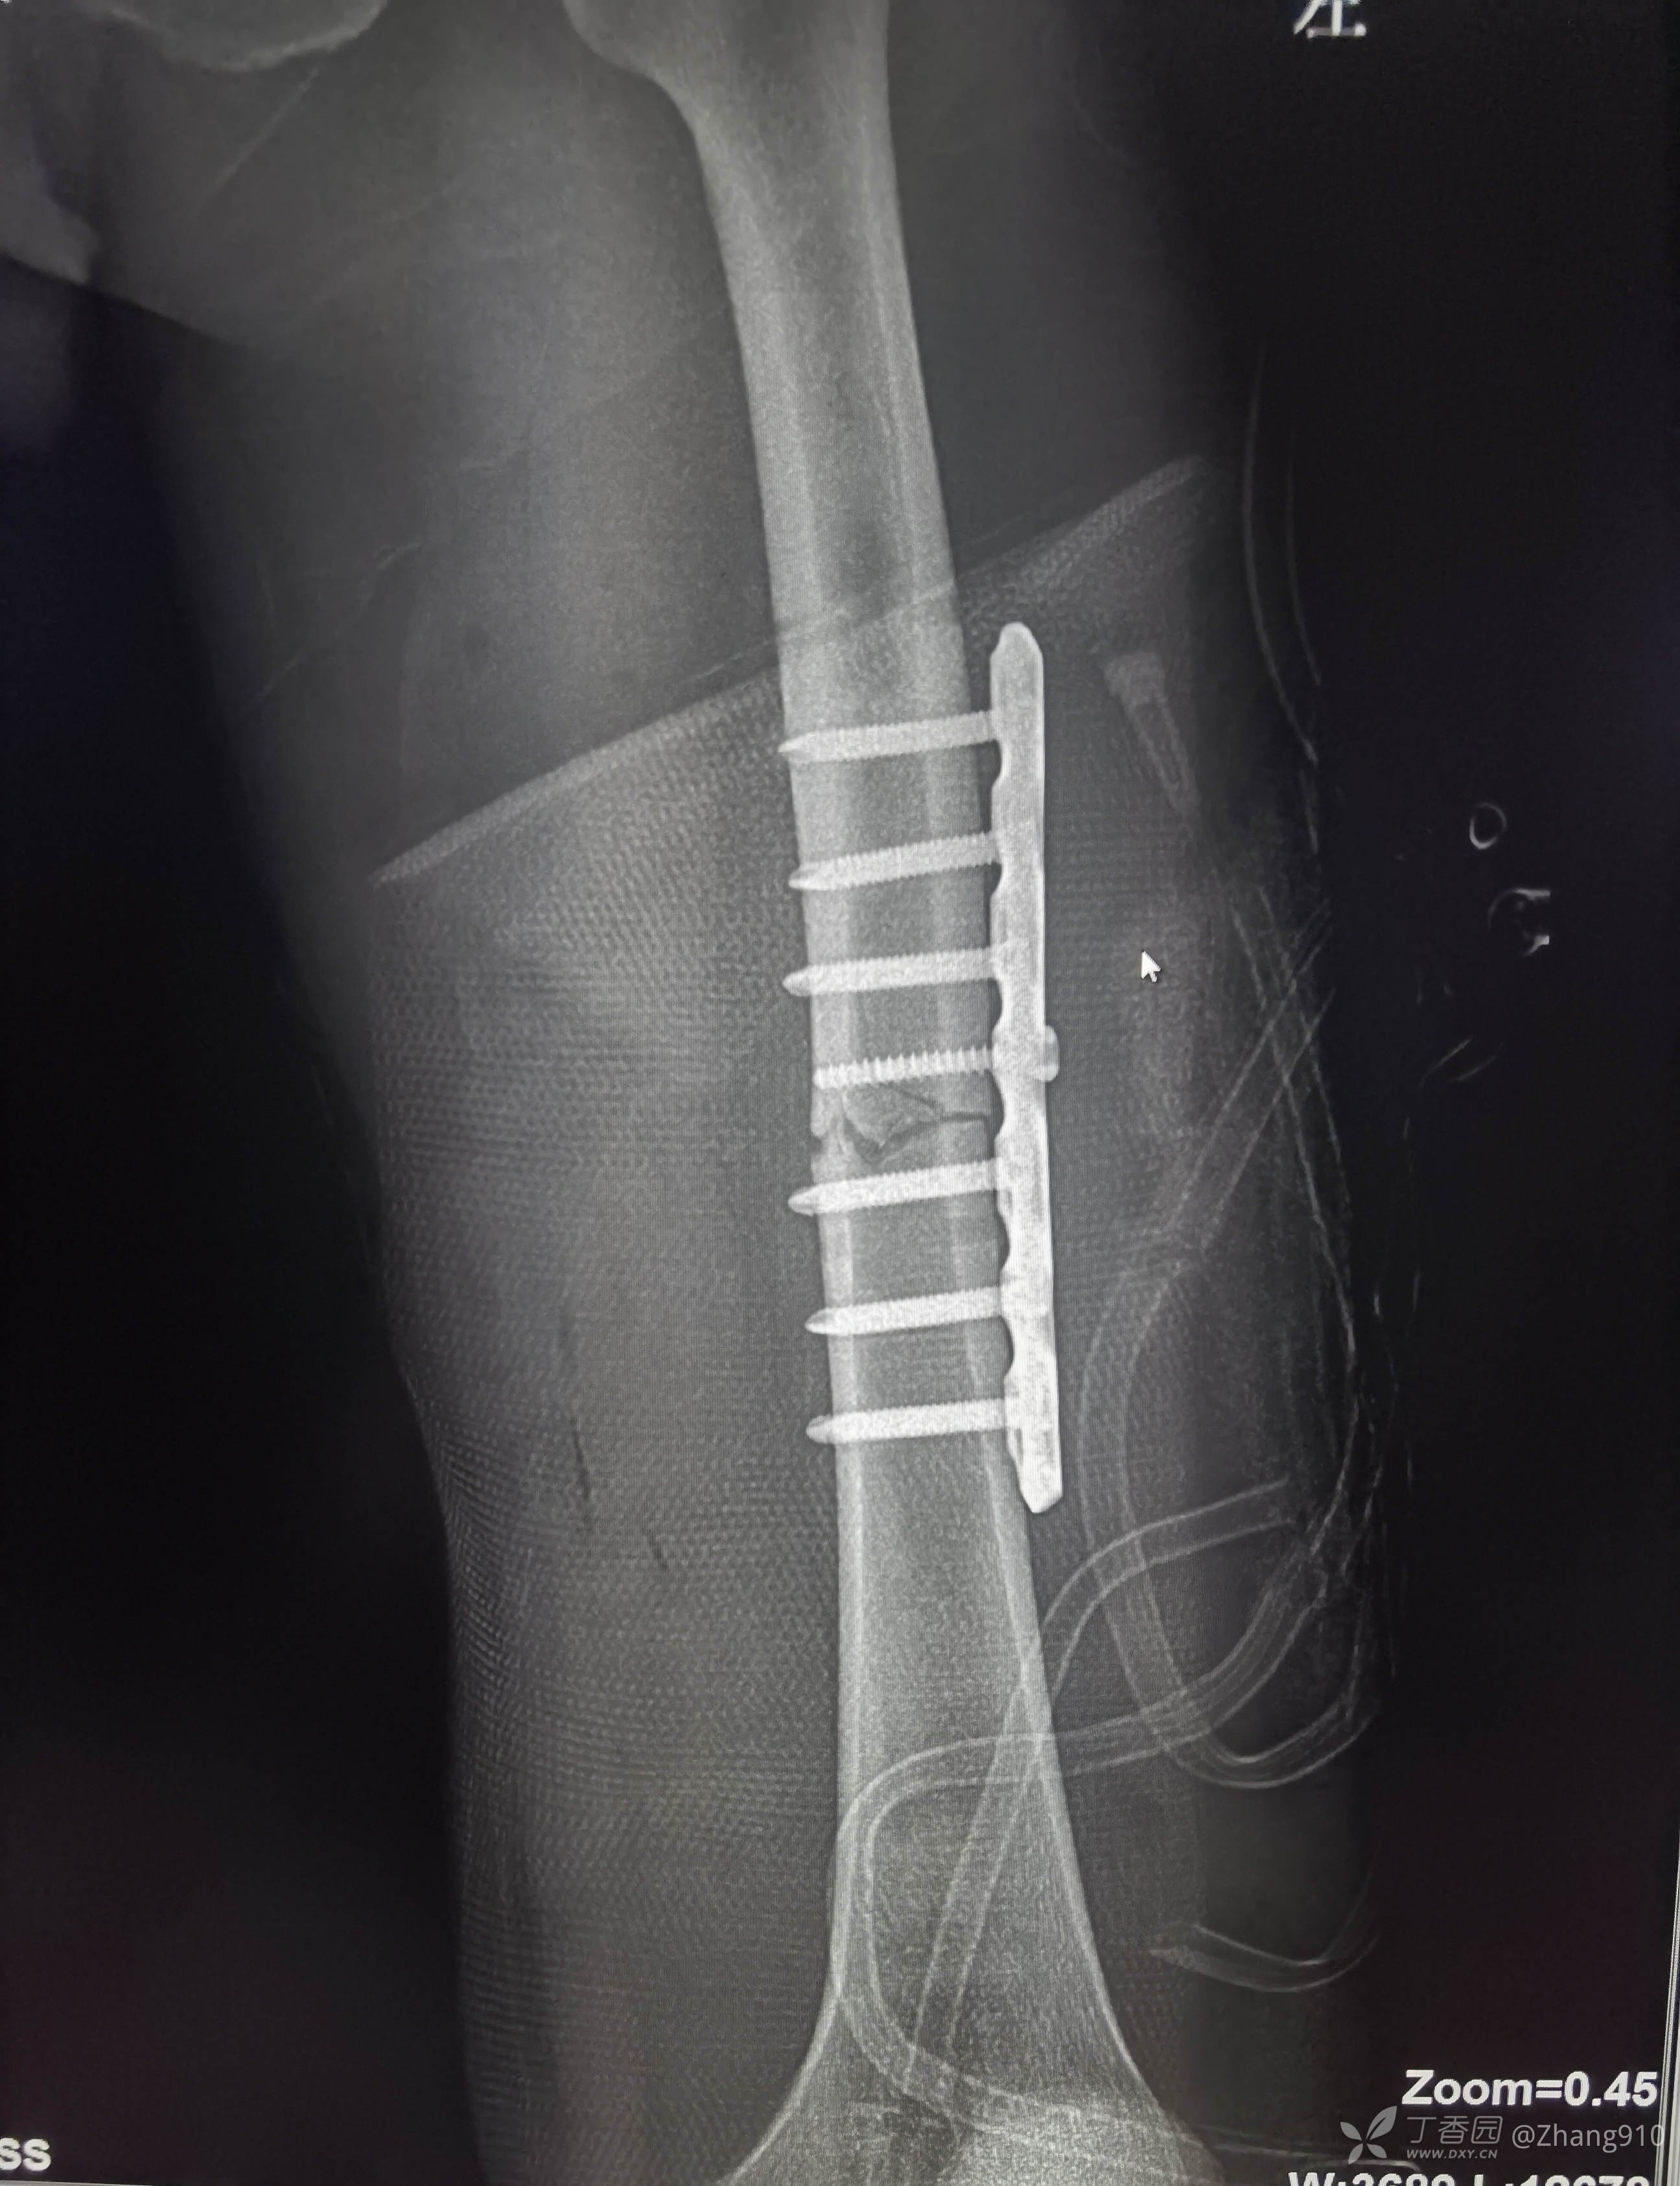

术后x线:如下图

当时股骨颈骨折情况: